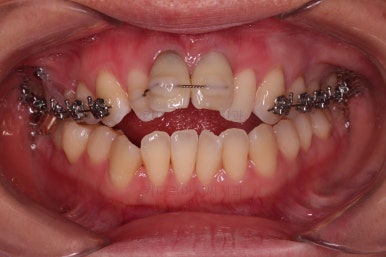

3. 치료과정

개방교합을 닫는 전략은 앞니를 약간 끌어내리고, 어금니를 앞니 위치로 약간 올려서 균형을 맞추는 건데요.

장치 부착은 윗니 어금니부터 했습니다.

미니스크류를 다양하게 활용하여 어금니 높이를 조절합니다.

여전히 앞니는 내버려둔 채로, 윗니는 어금니쪽만 진행하며 아랫니도 장치를 부착했습니다.

난이도가 매우 높은 치료인만큼 미니스크류의 구성과 장치 구성도 매우 복잡했는데요.

윗니 어금니를 뒤로 밀면서 앵글씨 2급 부정교합을 개선해 주고, 높낮이를 조절하면서 개방교합을 개선해 줍니다.